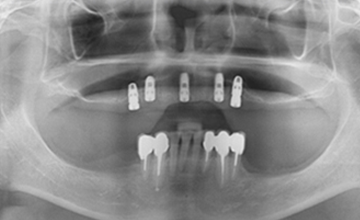

여러 개의 임플란트를 심은 뒤, 그 사이를 금속 막대로 연결해 튼튼한 지지대를

만들고, 그 위에 틀니를 안정적으로 고정하는 방식입니다.

몇 개의 임플란트를 심은 뒤, 완성된 임플란트에 부분 틀니를 연결해

흔들림 없이 안정감 있게 사용할 수 있으며 스스로 탈착은 불가능합니다.